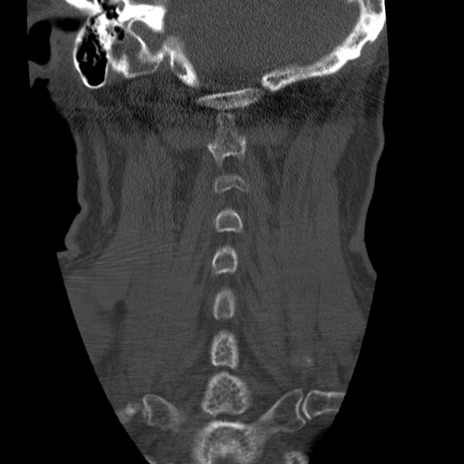

症例50 頚椎CT(冠状断像)

頚椎CT

矢状断像